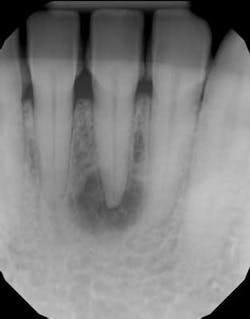

There are many etiologies behind the development of a radiolucent lesion at the apex of a tooth root. What clinicians are most familiar with are lesions of endodontic origin. Most of the time a dentist will see a radiolucency at the apex of the tooth, hopefully will test for vitality as well as perform other diagnostic tests, and if the tooth is nonvital will perform the root canal or refer it to a specialist who will accomplish this treatment. There are times, however, that tooth vitality is not checked and root canal treatment is simply initiated. The problem with this approach is that if the lesion is of nonendodontic origin, this treatment will not resolve the problem, and the lesion can expand in size even after the root canal is completed. These teeth can then be referred for apicoectomy or extraction with subsequent implant placement because of perceived root canal failure. Once again, because of improper diagnosis, these aggressive treatments may not take care of the original etiology behind the lesion.

Radiographic bone changes that mimic lesions of endodontic origin can include neoplasms as well as developmental alterations. (1) The differential diagnosis behind a unilocular radiolucent lesion that can look like a typical periapical radiolucency (PAR) of endodontic origin includes: periapical cemento-osseous dysplasia (figure 1), ameloblastoma, odontogenic keratocyst, central giant cell granuloma, traumatic bone cyst, and central ossifying fibroma.

Imagine this scenario: A dentist notices a radiographic radiolucency at the apex of a tooth during an exam and improperly initiates root canal therapy without taking the necessary diagnostic steps (vitality test, CBCT, clinical evaluation, etc.) on a tooth with an etiology other than endodontic origin. The lesion doesn’t resolve and the decision is made to extract the tooth with subsequent implant therapy. The implant is placed, and a few months later, an expanding radiolucency is now noted at the base of the implant. The implant is now deemed a failure with subsequent removal and regrafting.